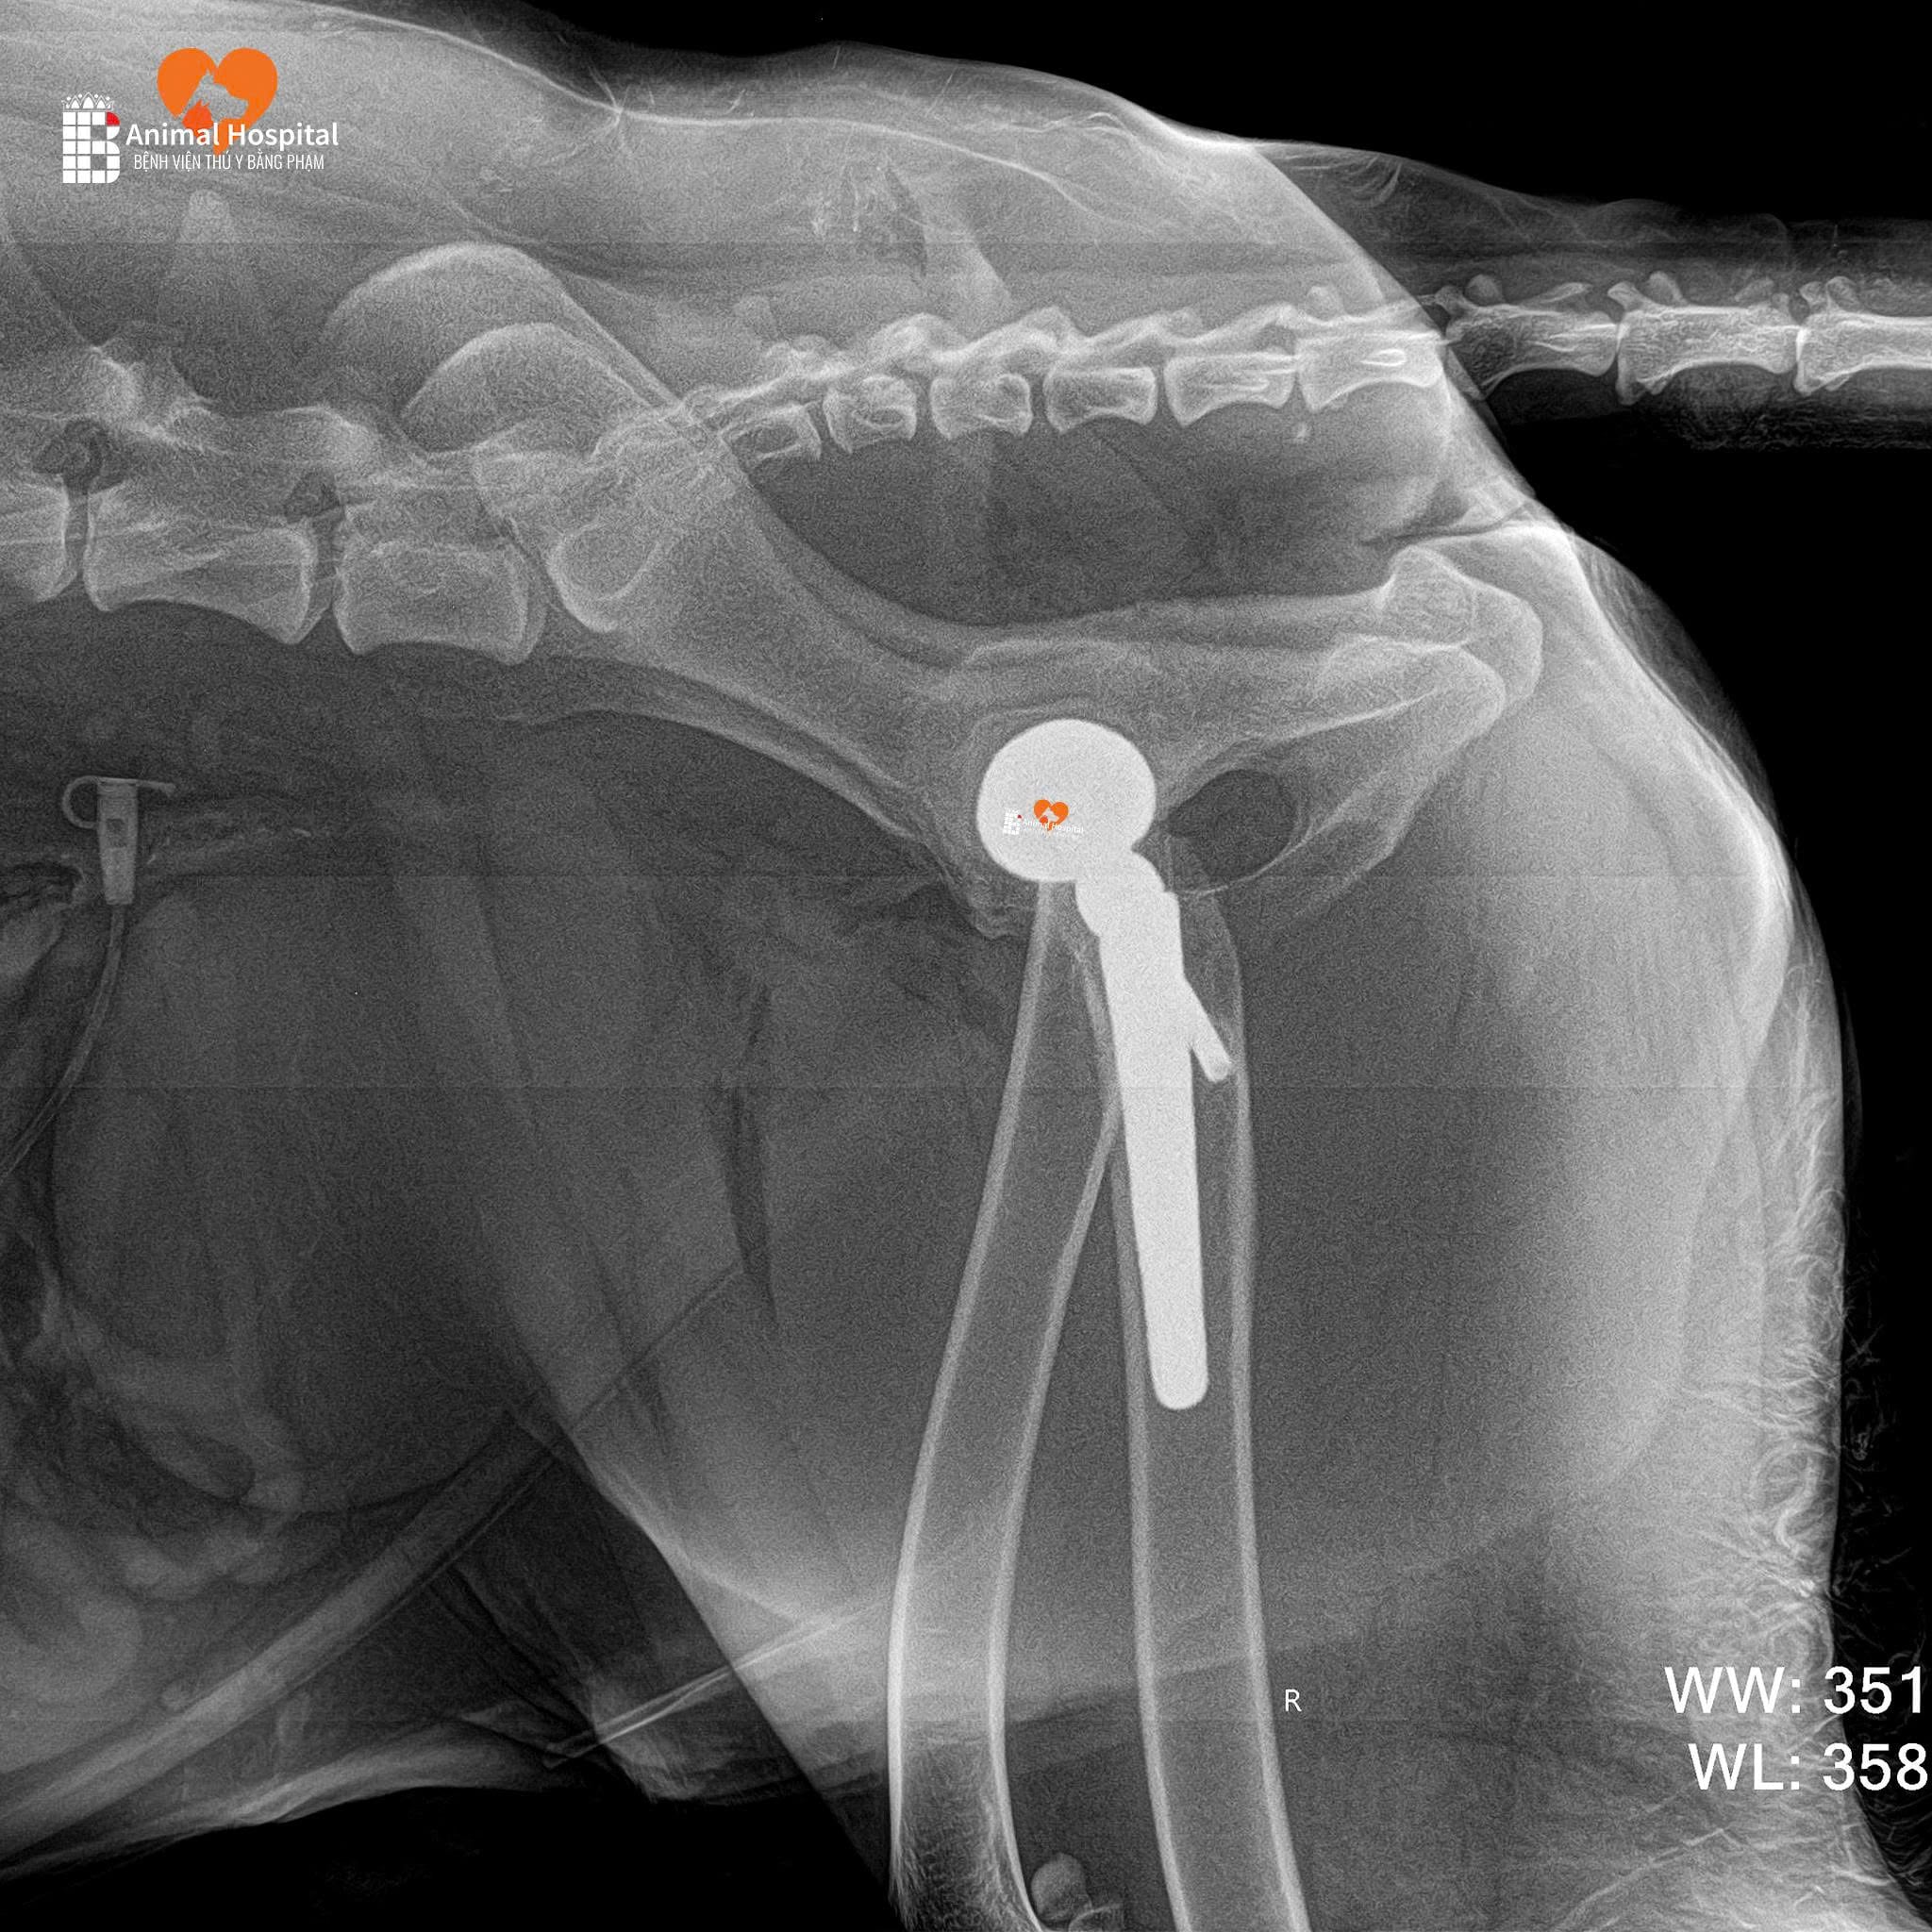

⚙️ Cấu hình sử dụng | Implant Configuration

- Chỏm đùi: PEEK 20mm

- Cup acetabulum: Titan không xi măng 25mm

- Thân femur: Không xi măng size #8

- Cổ xương: Size 0

- Ốc bên: 22mm cố định cup

Ảnh X-quang hậu phẫu cho thấy:

- Implant được đặt đúng vị trí

- Trục khớp chuẩn xác

- Tiếp xúc xương tốt – là tiền đề lý tưởng cho sự phục hồi.